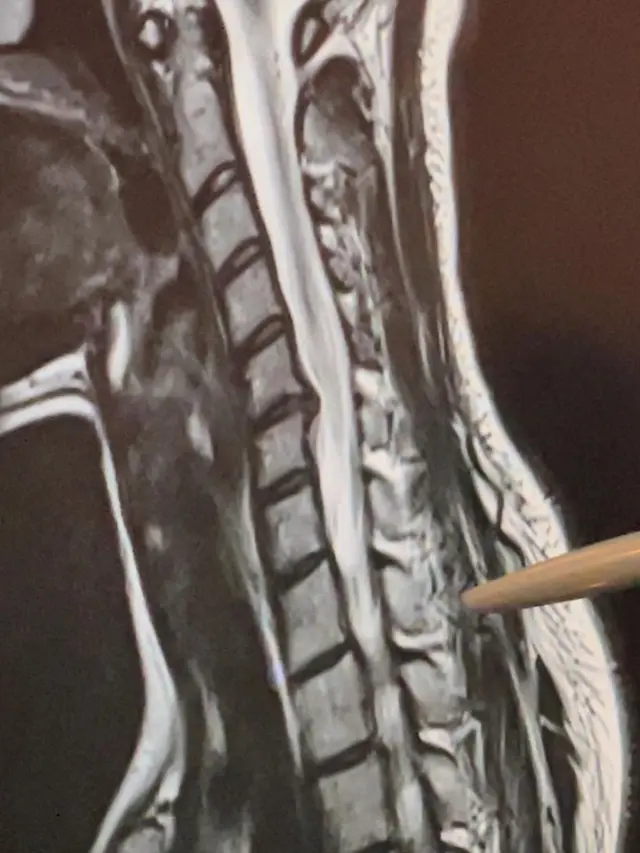

Fimela.com, Jakarta Baru-baru ini, Sheryl Sheinafia menyampaikan kabar yang kurang menyenangkan perihal kesehatannya. Pasalnya ia mengaku mengalami gangguan herniasi diskus atau cedera hernia tulang belakang yang biasanya disebut saraf kejepit.

Gangguan tersebut dirasakan Sheryl sepekan setelah ia merayakan ulang tahunnya pada Desember 2021 lalu. Bahkan perempuan berwajah cantik ini mengalami sakit yang luar biasa di bagian leher.

Ia memperliahtkan potret mulai dari tempat terapi, lehernya yang disangga, hingga hasil roentgen leher. Dalam keterangan foto, Sheryl mengungkapkan jika kondisi lehernya sempat mengalami sakit yang sangat parah.

"Seminggu setelah ulang tahunku, mengalami rasa sakit luar biasa dari leher dan lengan kanan sampai pada saat bermain gitar, menulis dan hanya duduk tanpa sandaran memberiku masalah seperti sakit kepala dan mati rasa," tulisnya.

Sheryl menjelaskan jika gangguan ini disebabkan karena kebiasaan buruknya. "Pada dasarnya, aku memiliki kebiasaan yang sangat buruk untuk maju ke depan. herniasi diskus tidak hanya untuk orang tua, jadi jangan lupa untuk sesekali berdiri ketika kamu duduk atau meregangkan lehermu sesekali," lanjutnya.